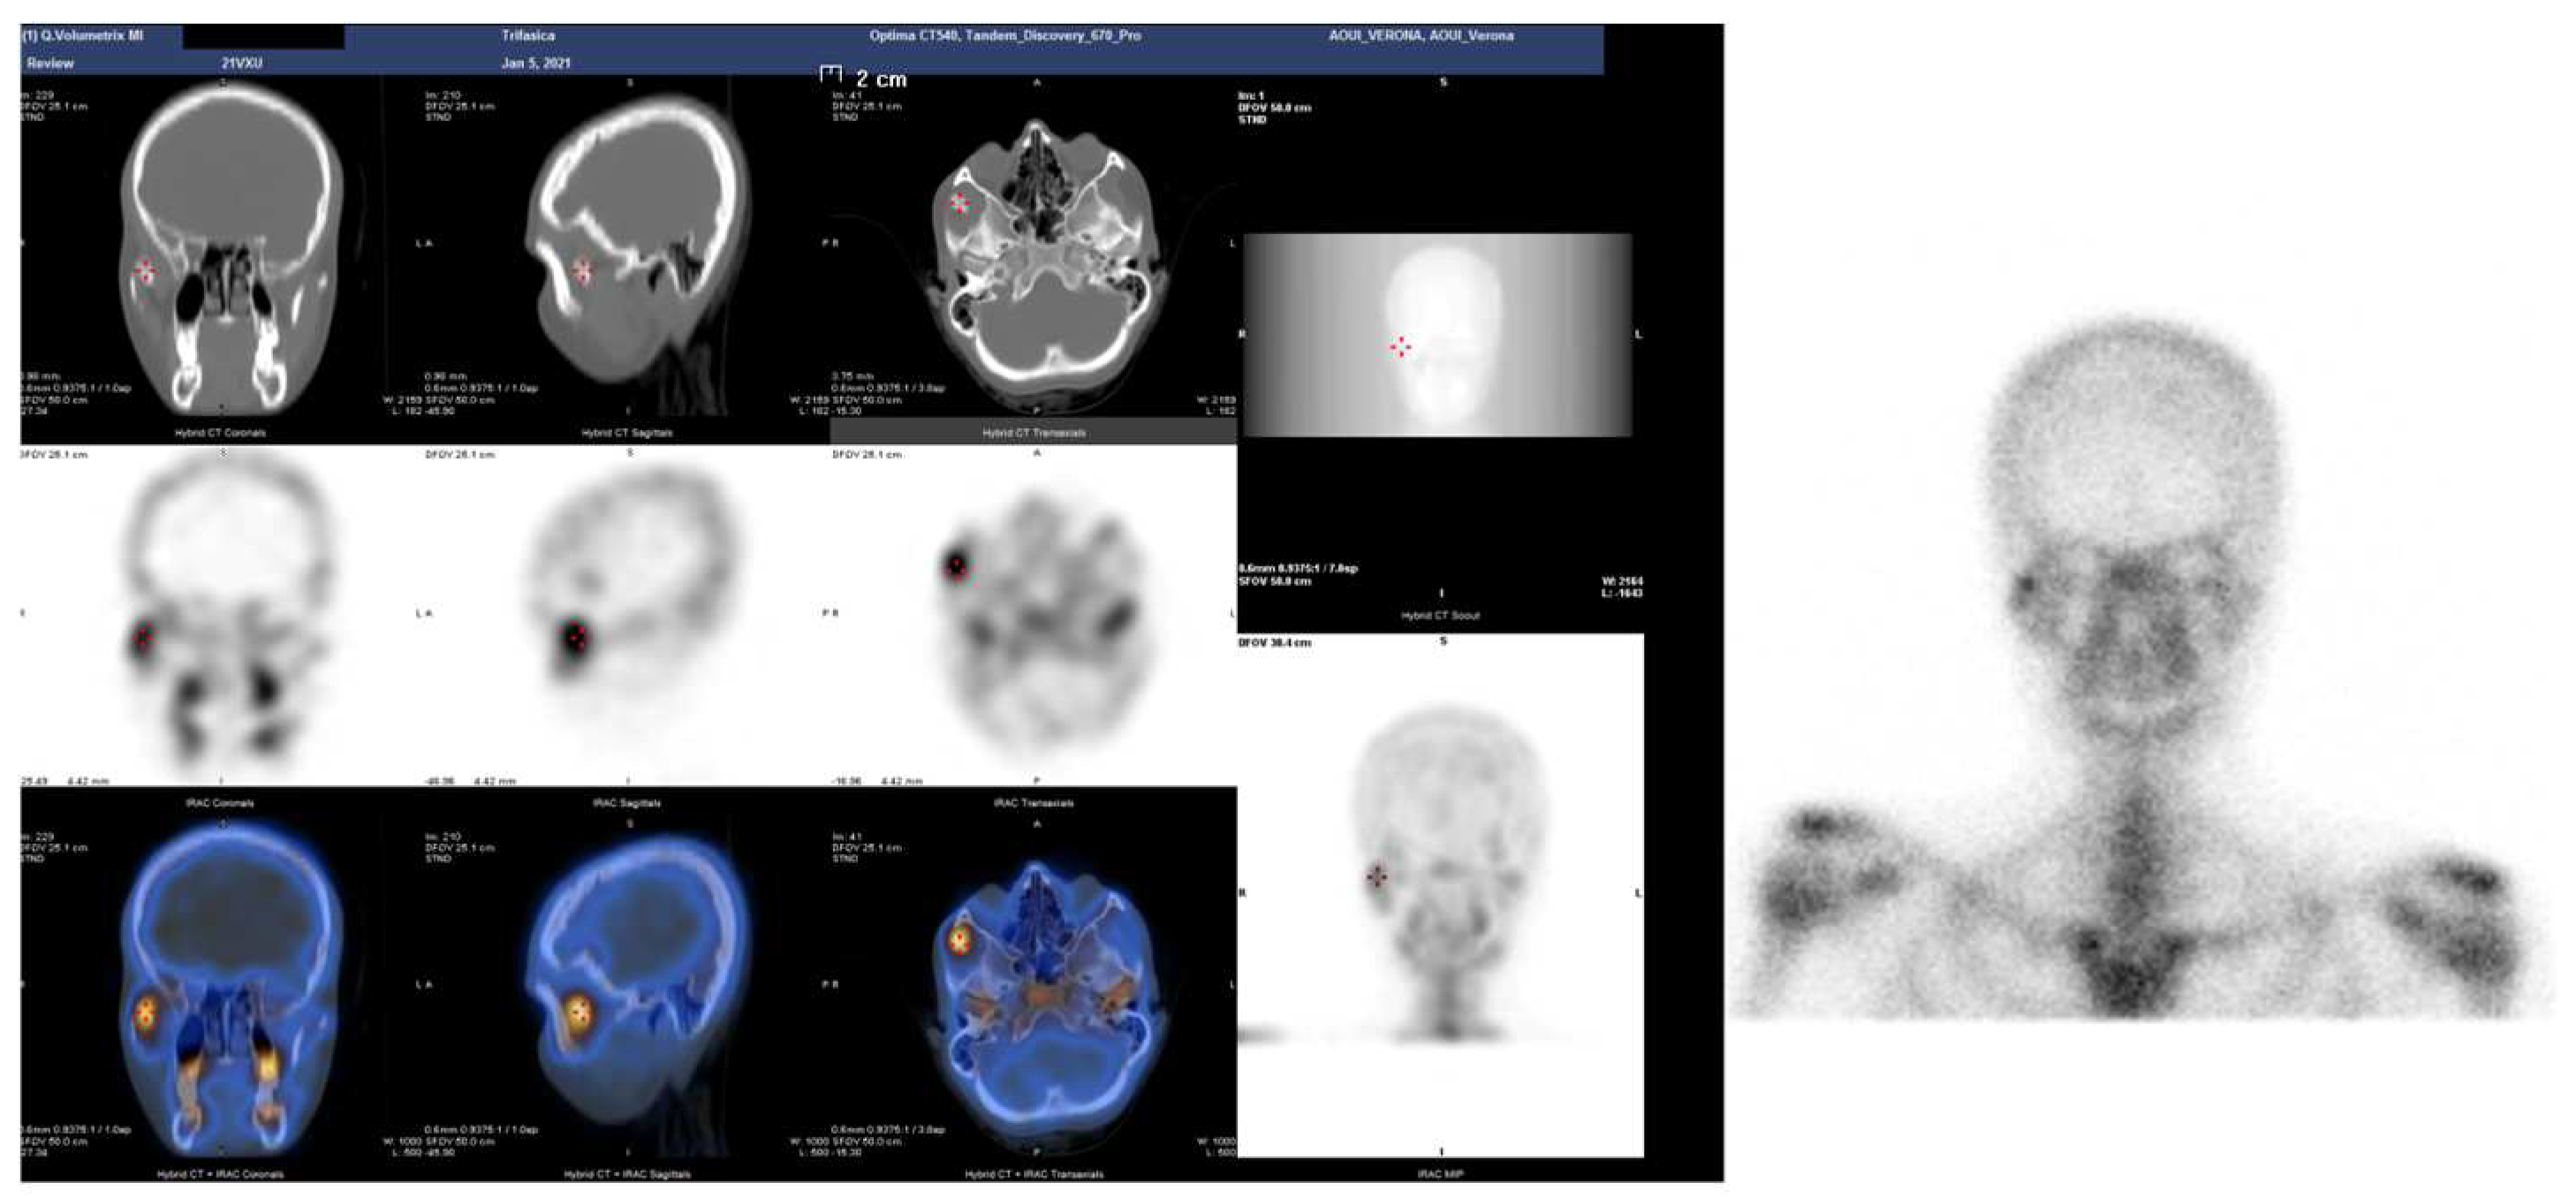

Figure 3.

SPET-CT showing bone reworking in correspondence to the joint between the jaw and the right zygomatic bone compared to the contralateral homologous site.

A 19-year-old woman was referred to us, presenting with a history of progressive limitation in mouth opening over the previous 18 months. She complained of a dull pain just in front of her right ear, exacerbated by palpation and mandibular movements. She had no medical history and did not report any previous local trauma. She was initially diagnosed with temporomandibular disease (TMD) dysfunction and treated conservatively with an occlusal bite with no symptomatologic relief. At physical examination, the maximum mouth opening (MMO) was reduced to 25 mm, but mandibular movements were preserved. No articular noises during temporomandibular joint (TMJ) bilateral palpation were perceived, but she complained of pain in the masticatory muscles bilaterally. No malocclusion, facial asymmetry or swelling were identified. The orthopantomogram (OPG) (Figure 1) and the magnetic resonance imaging (MRI) were negative. Given the absence of clinical improvement but a rather slow and progressive reduction in MMO, a computed tomography (CT) was performed, revealing an enlargement and an abnormally shaped right CPM, establishing a close relationship with the zygomatic arch (Figure 2). Furthermore, single-photon emission computed tomography (SPECT) was prescribed, and the late images of bone uptake showed a focal increase in the correspondence of the so-called pseudojoint between the jaw and the right zygomatic bone compared to the left side (Figure 3). According to this, a provisional diagnosis of JD was made. The patient underwent a right coronoidectomy through an intraoral approach under general anesthesia with awake, blind, nasal intubation. The right, mushroom-shaped coronoid process was identified and resected, and a sort of fibrotic capsule between the inner aspect of the zygoma and the CPM was highlighted, establishing the pseudojoint, with this confirming the diagnosis of JD (Figure 4). Histopathologically, the specimen showed a growth pattern of hyperplastic bone tissue covered by cartilaginous layers and an external coating of dense fibrous tissue. There were no intra-operative or immediate postoperative complications. Postoperative CT was obtained for baseline follow-up. The MMO increased to about 30 mm in the immediate postoperative period, and this improved to 40 mm after a month of aggressive physiotherapy. She underwent clinical and radiological follow-up, and after 12 months, the MMO was stable, and no recurrence was observed.